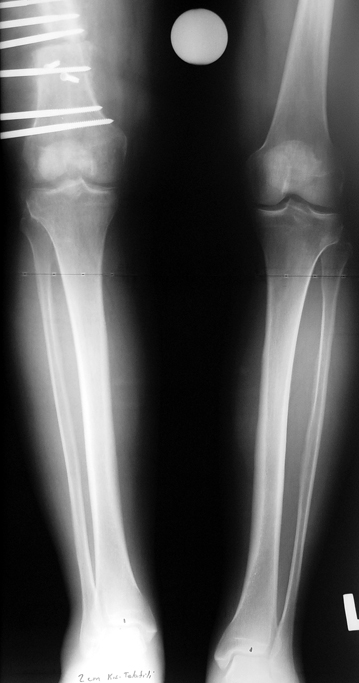

Appropriate radical debridement necessitates excision of all necrotic bone and soft tissues, and frequently causes instability at the involved extremity. The remaining bone and soft tissue defect has to be fixed and reconstructed. The distraction osteogenesis method of Ilizarov is used successfully for achievement of union, correction of the deformity, elimination of limb length inequality and reconstruction of segmental bone defects.

The duration of external fixation (external fixation index) depends on the amount of distraction required, and the extremity is prone to complications during this period. After the distraction phase is completed, the external fixator remains in place during the consolidation phase, which lasts twice as long as the distraction phase; but this period is hardly tolerated. If the external fixator is removed before sufficient consolidation is achieved, fractures, deformity and shortness will be the result. In our department, ‘lenghthening over nail’ method is used in order to decrease the external fixation index and increase patient comfort and activity level. In this method, the intramedullary nail is statically locked after the completion of the distraction phase, and external fixator is removed. The extremity is stabilized by the intramedullary nail during consolidation phase. In this way, complications due to long external fixation index or early removal of the external fixator are avoided.

Case 2